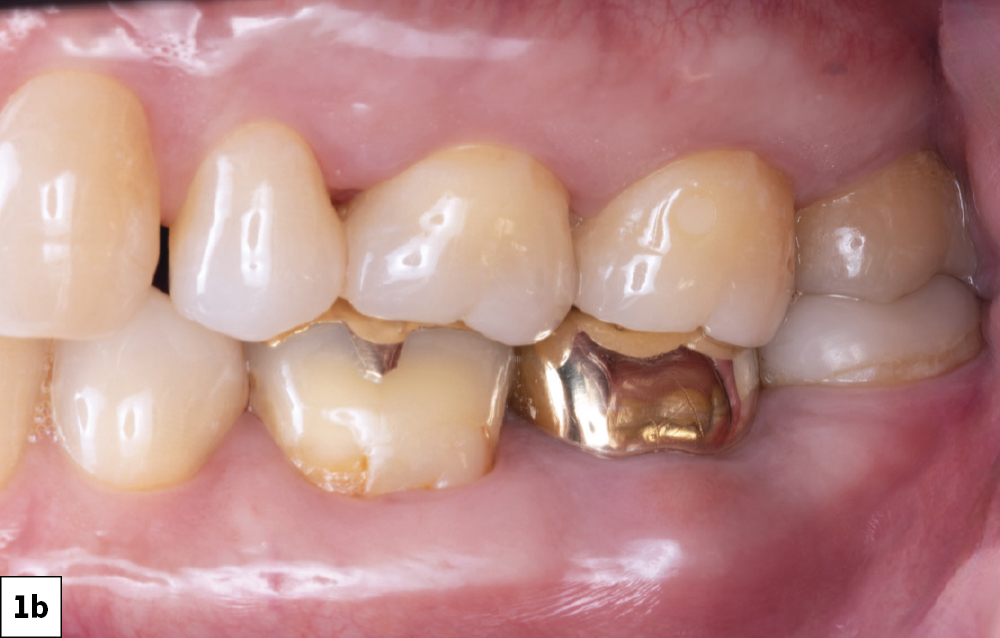

In-office milling is a quickly evolving option for the modern dental practice. With the introduction of a same-day screw-retained option, BruxZir® NOW SRC milling blocks, there’s even more opportunity for optimizing single-unit restoration workflows. In this case study, I’ll demonstrate how this product can be used as part of an efficient workflow for tooth replacement in the posterior. When combined with guided surgery and in-office crown design, this procedure offers reliable results while saving money and significantly cutting down on chair time for dentists.

Increased sophistication of in-office crown design software gives dentists more control over restorations they mill in their own practice. More streamlined workflows in surgical and restorative phases means more predictability, repeatability, and long-term success for these essential procedures. By reducing the likelihood of surgical errors with guided implant surgery and cutting down on in-lab working times with in-office milling, clinicians can provide great services while continuing to increase revenue.